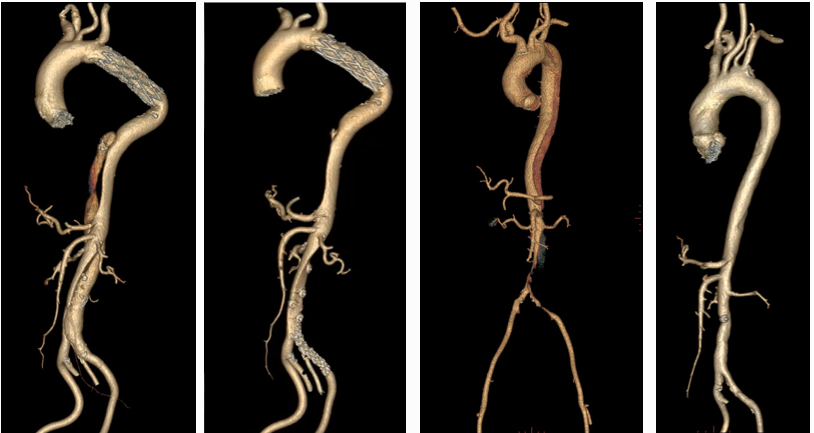

★ 其他技术

1. 假腔栓塞技术

2. 杂交手术:开窗/分支支架重建内脏动脉

3. 平行支架技术

4. 覆膜支架技术

5. 逆向分支技术

6. 3D打印辅助开窗技术

7. G-Branch支架系统:多分支一体化重建内脏动脉

8. VSD封堵伞封堵破口